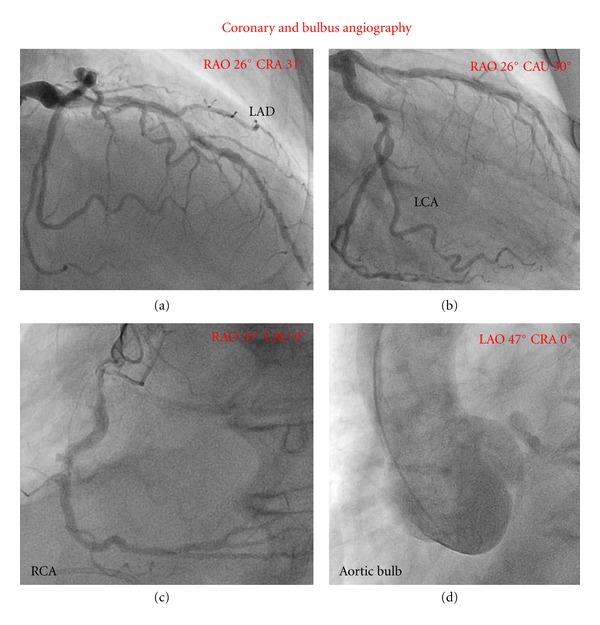

Annuloaortic ectasia is a relatively rare diagnosis. Herein, we report an unusual case of an annuloaortic ectasia with asymmetric dilatation of the right coronary bulb mimicking a membranous ventricular septal defect (VSD) with Eisenmenger reaction by transthoracic echocardiography. Aortic angiography showed a dilated aortic root and moderate aortic regurgitation. Right cardiac catheterization, on the other hand, exhibited normal pulmonary artery blood pressure and normal pulmonary resistance, whereas normal venous gas values were measured throughout the caval vein and the right atrium, excluding relevant left-right shunting. Further diagnostic workup by cardiac computed tomography angiography (CCTA) unambiguously illustrated the asymmetric geometry of the ectatic aortic cusp and root causing compression of the right heart and of the right ventricular (RV) outflow tract. After review of echocardiographic acquisitions, the blood flow detected between the left and right ventricles (mimicking VSD) was interpreted as turbulent inflow from the left ventricle into the ectatic right coronary cusp. Furthermore, elevated pulmonary artery blood pressure measured by echocardiography was attributed to "functional pulmonary stenosis" due to compression of the RV outflow tract by the aorta, as demonstrated by CCTA.

升主动脉瘤样扩张是一种相对罕见的诊断。在此,我们报告一例不寻常的升主动脉瘤样扩张病例,经胸超声心动图显示右冠状动脉窦不对称扩张,类似膜周部室间隔缺损(VSD)并伴有艾森曼格反应。主动脉造影显示主动脉根部扩张和中度主动脉瓣反流。另一方面,右心导管检查显示肺动脉血压和肺阻力正常,而在整个腔静脉和右心房测量的静脉血气值正常,排除了相关的左右分流。通过心脏计算机断层血管造影(CCTA)进行的进一步诊断检查明确显示了扩张的主动脉瓣尖和根部的不对称形态,导致右心和右心室(RV)流出道受压。在回顾超声心动图图像后,左、右心室之间检测到的血流(类似VSD)被解释为从左心室进入扩张的右冠状动脉窦的湍流。此外,如CCTA所示,超声心动图测量的肺动脉血压升高归因于主动脉对RV流出道的压迫导致的“功能性肺动脉狭窄”。